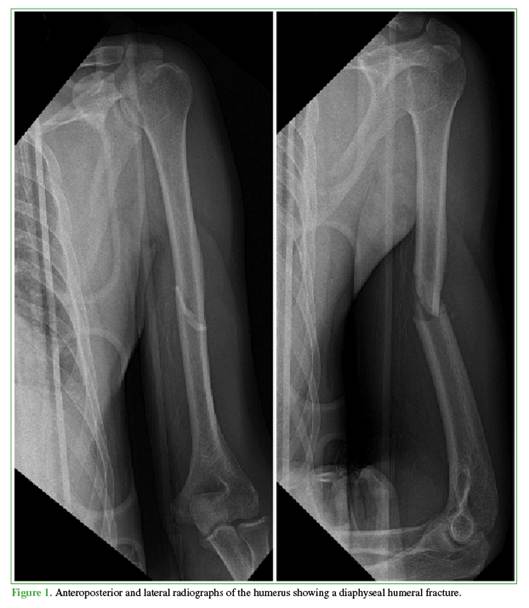

Preoperatively, all patients underwent anteroposterior and lateral radiographs including the shoulder and elbow to characterize the fracture pattern, malalignment and displacement, classification, joint involvement, and for preoperative planning (Figure 1). Computed tomography was not routinely obtained and was reserved for cases with suspected delayed union or nonunion.